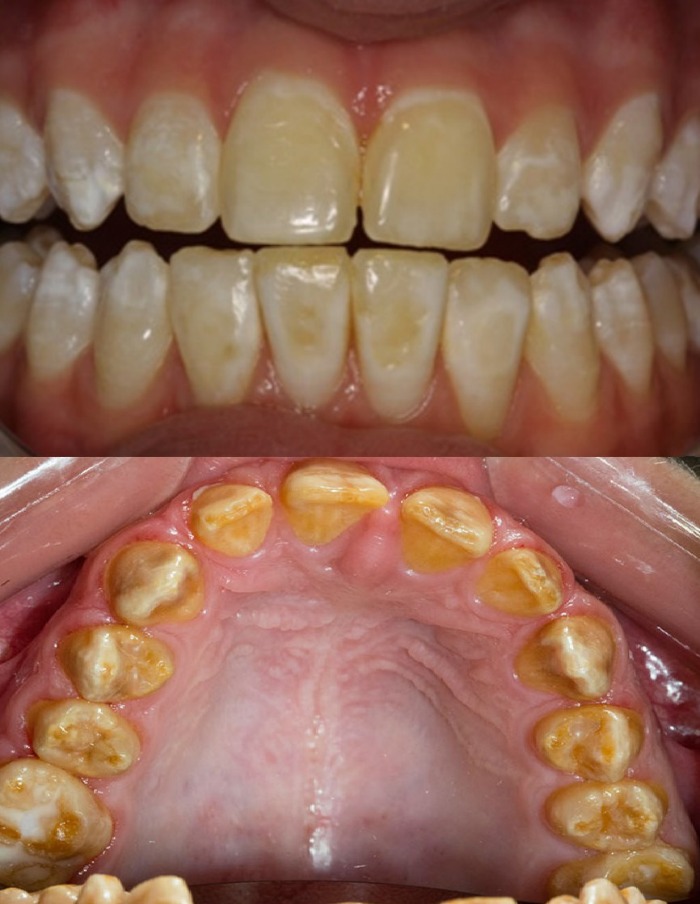

Отмечаются значительные вариации клинической картины ННА в зависимости от его типа. Наиболее тяжелой формой ННА является гипоплазия эмали, при которой во время проведения клинического и рентгенографического обследования выявляется практически полное отсутствие слоя эмали.

Однако чаще всего при гипопластическом типе ННА слой эмали становится истонченным, испещренным бороздками, приобретает желто-коричневый оттенок и грубую пористую текстуру. Наличие мягкой, непрозрачной эмали крапчато-белого, желтого или коричневого оттенка свидетельствует о ННА гипоматурационного типа. При гипокальцифицированном типе ННА эмаль, как правило, сильно стирается и с легкостью отделяется от подлежащего дентина. Утрата эмали при гипопластическом ННА сопровождается гистологическими изменениями дентина, который становится гиперминерализованным; таким образом, морфологическая структура пораженного дентина аналогична структуре склеротического дентина (Sanchez-Quevedo et al., 2004).

Основные клинические проблемы пациентов с ННА вне зависимости от его типа заключаются в неудовлетворительной эстетике зубного ряда, повышенной чувствительности и утрате вертикальной высоты прикуса вследствие повышенной стираемости твердых тканей зубов (Seow, 1993).

У 8 из 12 пациентов был обнаружен ННА гипопластического типа, в 2 из 12 случаев был диагностирован ННА гипоматурационного типа, еще в 2 клинических случаях был выявлен ННА гипокальцифицированного типа. Основные жалобы пациентов были связаны с неудовлетворительным эстетическим видом зубов и их повышенной чувствительностью. Состояние полости рта пациентов на момент включения в исследование показано в таблице № 1 .